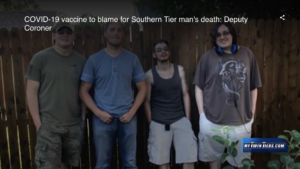

“I don’t know what else to do, or where to even go from here.” COVID-19 vaccine to blame for Southern Tier man’s death: Deputy Coroner

by: Tara Lynch

Posted: Feb 3, 2022 / 04:11 PM EST /

Posted: Feb 3, 2022 / 04:11 PM EST / Updated: Feb 9, 2022 / 04:09 PM EST

LOCKWOOD, N.Y. (WETM) — According to the Bradford County Deputy Coroner, a rare complication to the COVID-19 vaccine turned deadly for the Watts family of Lockwood. Their son, George Watts Jr.,… Read the rest